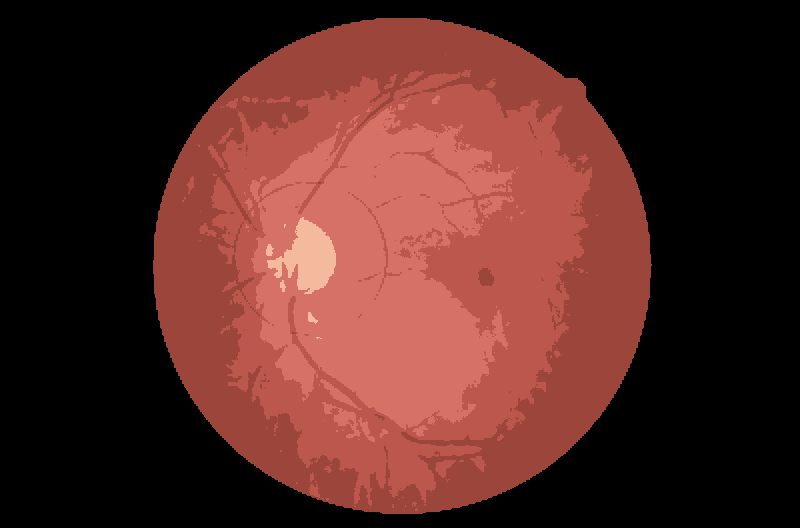

我正在尝试用python和openCV来实现视神经胶质瘤的鉴别。

为了成功地分类视神经胶质瘤,我需要做以下几个步骤。

我现在要做的是识别cv2.圆内图像的白色区域的大小。

如果我使用输出图像作为输入(在删除白色边框后):

cv2.waitKey(0)缩影图像:

阈值中白色像素的计数:

count = 1025729发布于 2020-02-29 01:09:03